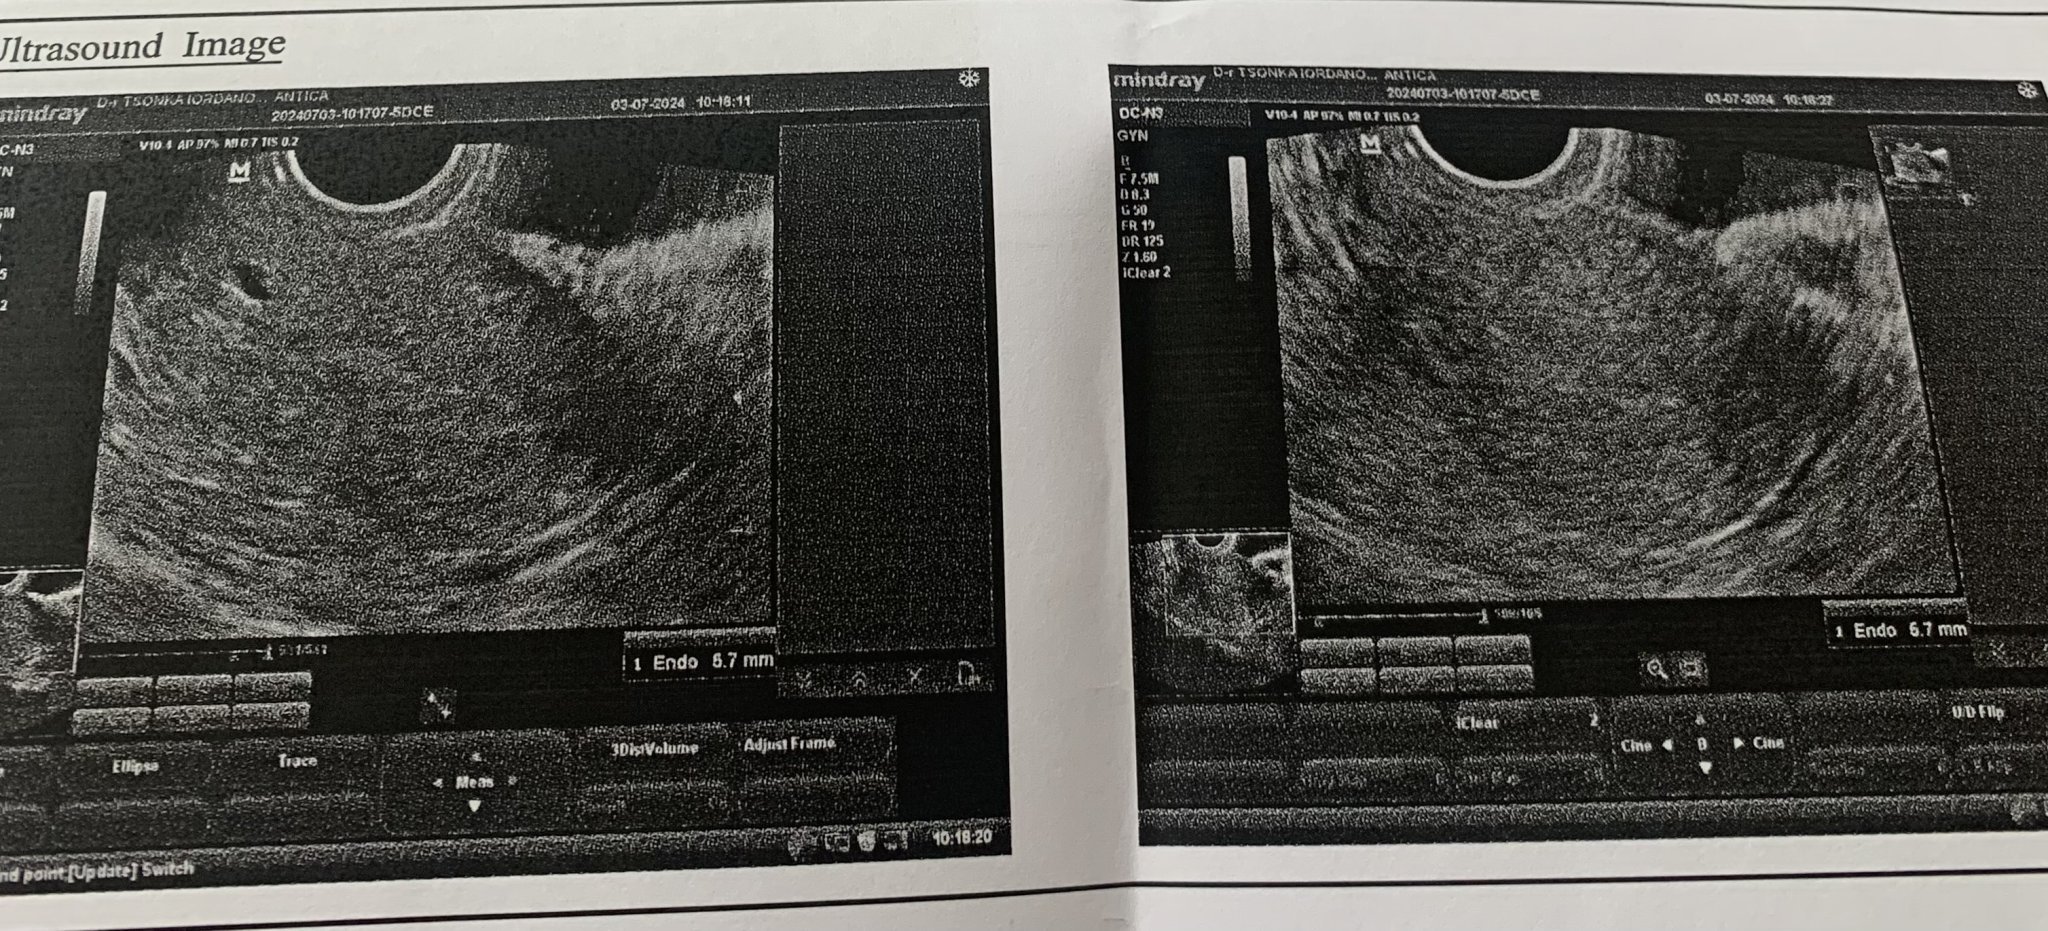

Здравейте,

Някой може ли да ми каже дали на ехографията , която прикачвам има сакче?

Благодаря,

Няма.

И все пак не сме лекари. Нали бяхте на лекар, той какво каза??